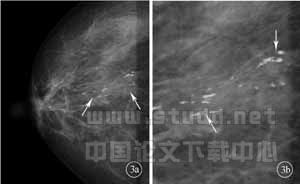

乳腺病变活检是乳腺癌术前确诊的重要环节,对于影像学(X线或超声成像)检查所发现的可疑恶性的微小钙化或小结节(图3、图4),需活检定性,但往往由于病变小,临床医师触诊阴性,造成活检困难或假阴性结果。乳腺导丝定位正是针对这种情况,在影像学(X线或超声)引导下进行病变穿刺,留置导丝于病变部位,引导外科医师对可疑恶性病变进行手术切除活检的定位方法。实践证明,乳腺导丝定位外科切除活检有利于乳腺癌的早期诊断,尤其对表现为微小钙化或微小结节的乳腺病变的定性具有突出的临床意义,是早期发现乳腺癌的有效手段。

图3 患者,女,60岁,右乳后方中纯杆状钙化,沿导管走行分布,x线和超声均正确诊断,超声引导下定位,病灶完整切除,术后病理:乳腺导管内癌(a:右乳轴位;b:轴位局部放大)

图4患者,女,61岁,左乳外下象限小结节影,直径0.7cm,形态不规则,X线检查和超声成像均正确诊断,超声引导下定位活检,病理诊断:乳腺浸润性筛状癌(a:左乳轴位;b:左乳斜位)